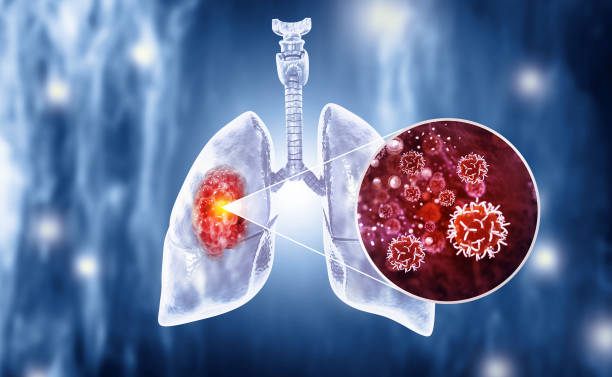

폐암은 폐에서 생기는 악성 종양으로, 결절이라고도 불립니다.

이러한 결절은 폐 내에 작은 덩어리 혹은 종양으로 나타날 수 있으며, 그 중에서도 양성과 악성 종양이 구분됩니다.

악성 종양은 일반적으로 암이라고 알려져 있으며, 폐암이라고도 불립니다.

폐암은 초기에는 증상이 미미하여 진단이 어려울 수 있습니다. 주로 호흡기 증상으로 나타나며, 기침, 가래, 혈올림, 흉통, 호흡곤란 등이 그 예입니다.

초기 폐암의 경우 종양의 크기가 작아서 통증이나 불쾌한 증상이 없을 수 있으며, 종양이 기관지 주변을 침범하거나 기관지 내부에 자극을 주면서 기침과 가래가 나타날 수 있습니다.